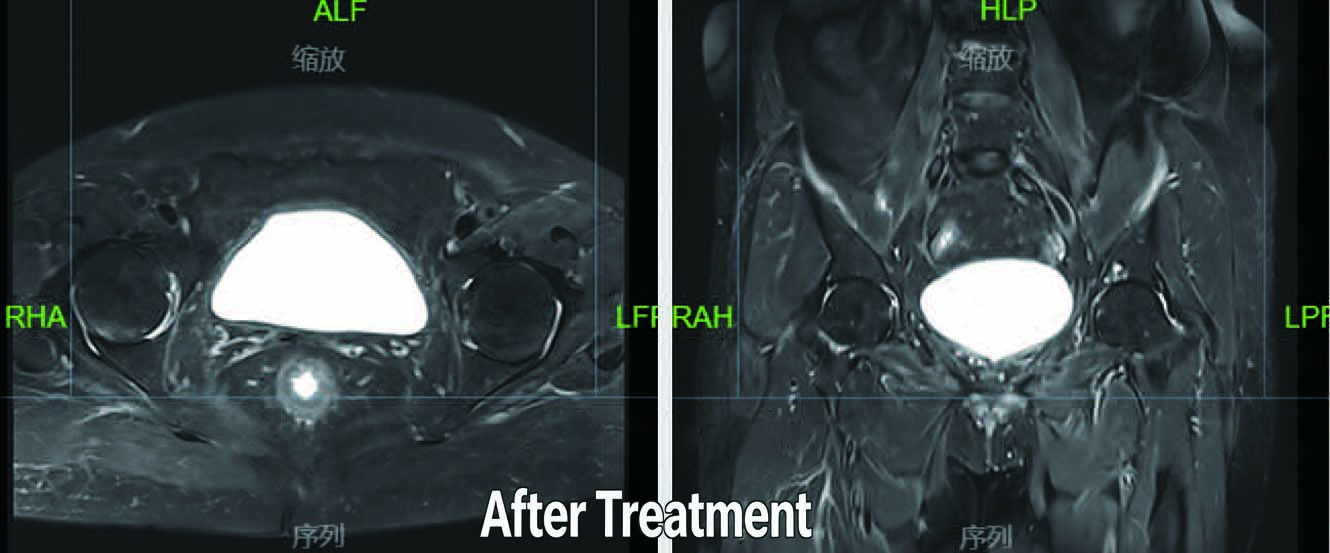

Patient: 59-year-old female

Diagnosis: Bladder Cancer

Treatment:March 29, 2021: PET/CT scan revealed multiple lesions in the anterior, posterior, and bottom walls of the bladder, suggestive of tumor recurrence.

Synchronous Chemoradiotherapy (Single-agent cisplatin 20 mg/m2 weekly)

Pelvic VMAT: 45 Gy to the pelvis, with a local boost of 20 Gy to the bladder, using image-guided radiation therapy (IGRT) Outcome:Post-radiotherapy pelvic MRI one month later showed no residual tumor or signs of recurrence in the bladder.